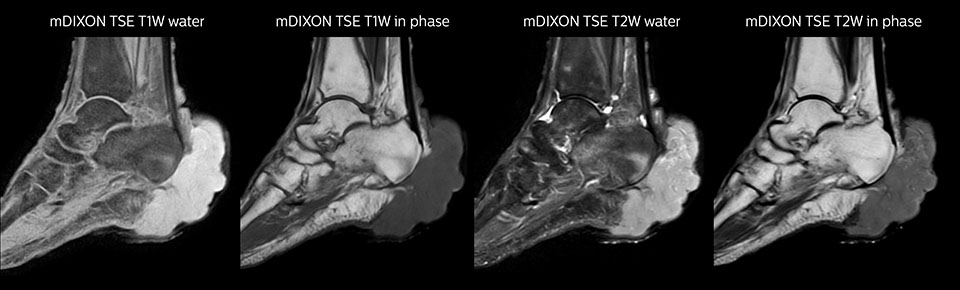

Shoulder MRI with high quality, large coverage

The Prodiva shoulder coil is very flexible and has large coverage, which makes good positioning easier, and that contributes to the superb image quality and high SNR that we get in our shoulder exams.

Scan time 2:55 min, FOV 160 mm,

acq voxels 0.55 x 0.83 x 3.0 mm.

Scan time 4:19 min, FOV 160 mm,

acq voxels 0.55 x 0.80 x 3.0 mm.

Scan time 2:50 min, FOV 160 mm,

acq voxels 0.70 x 0.99 x 3.0 mm.

Shoulder MRI with high quality, T2 SPIR

Shoulder MRI with high quality, mFFE

Shoulder MRI with high quality, STIR TSE